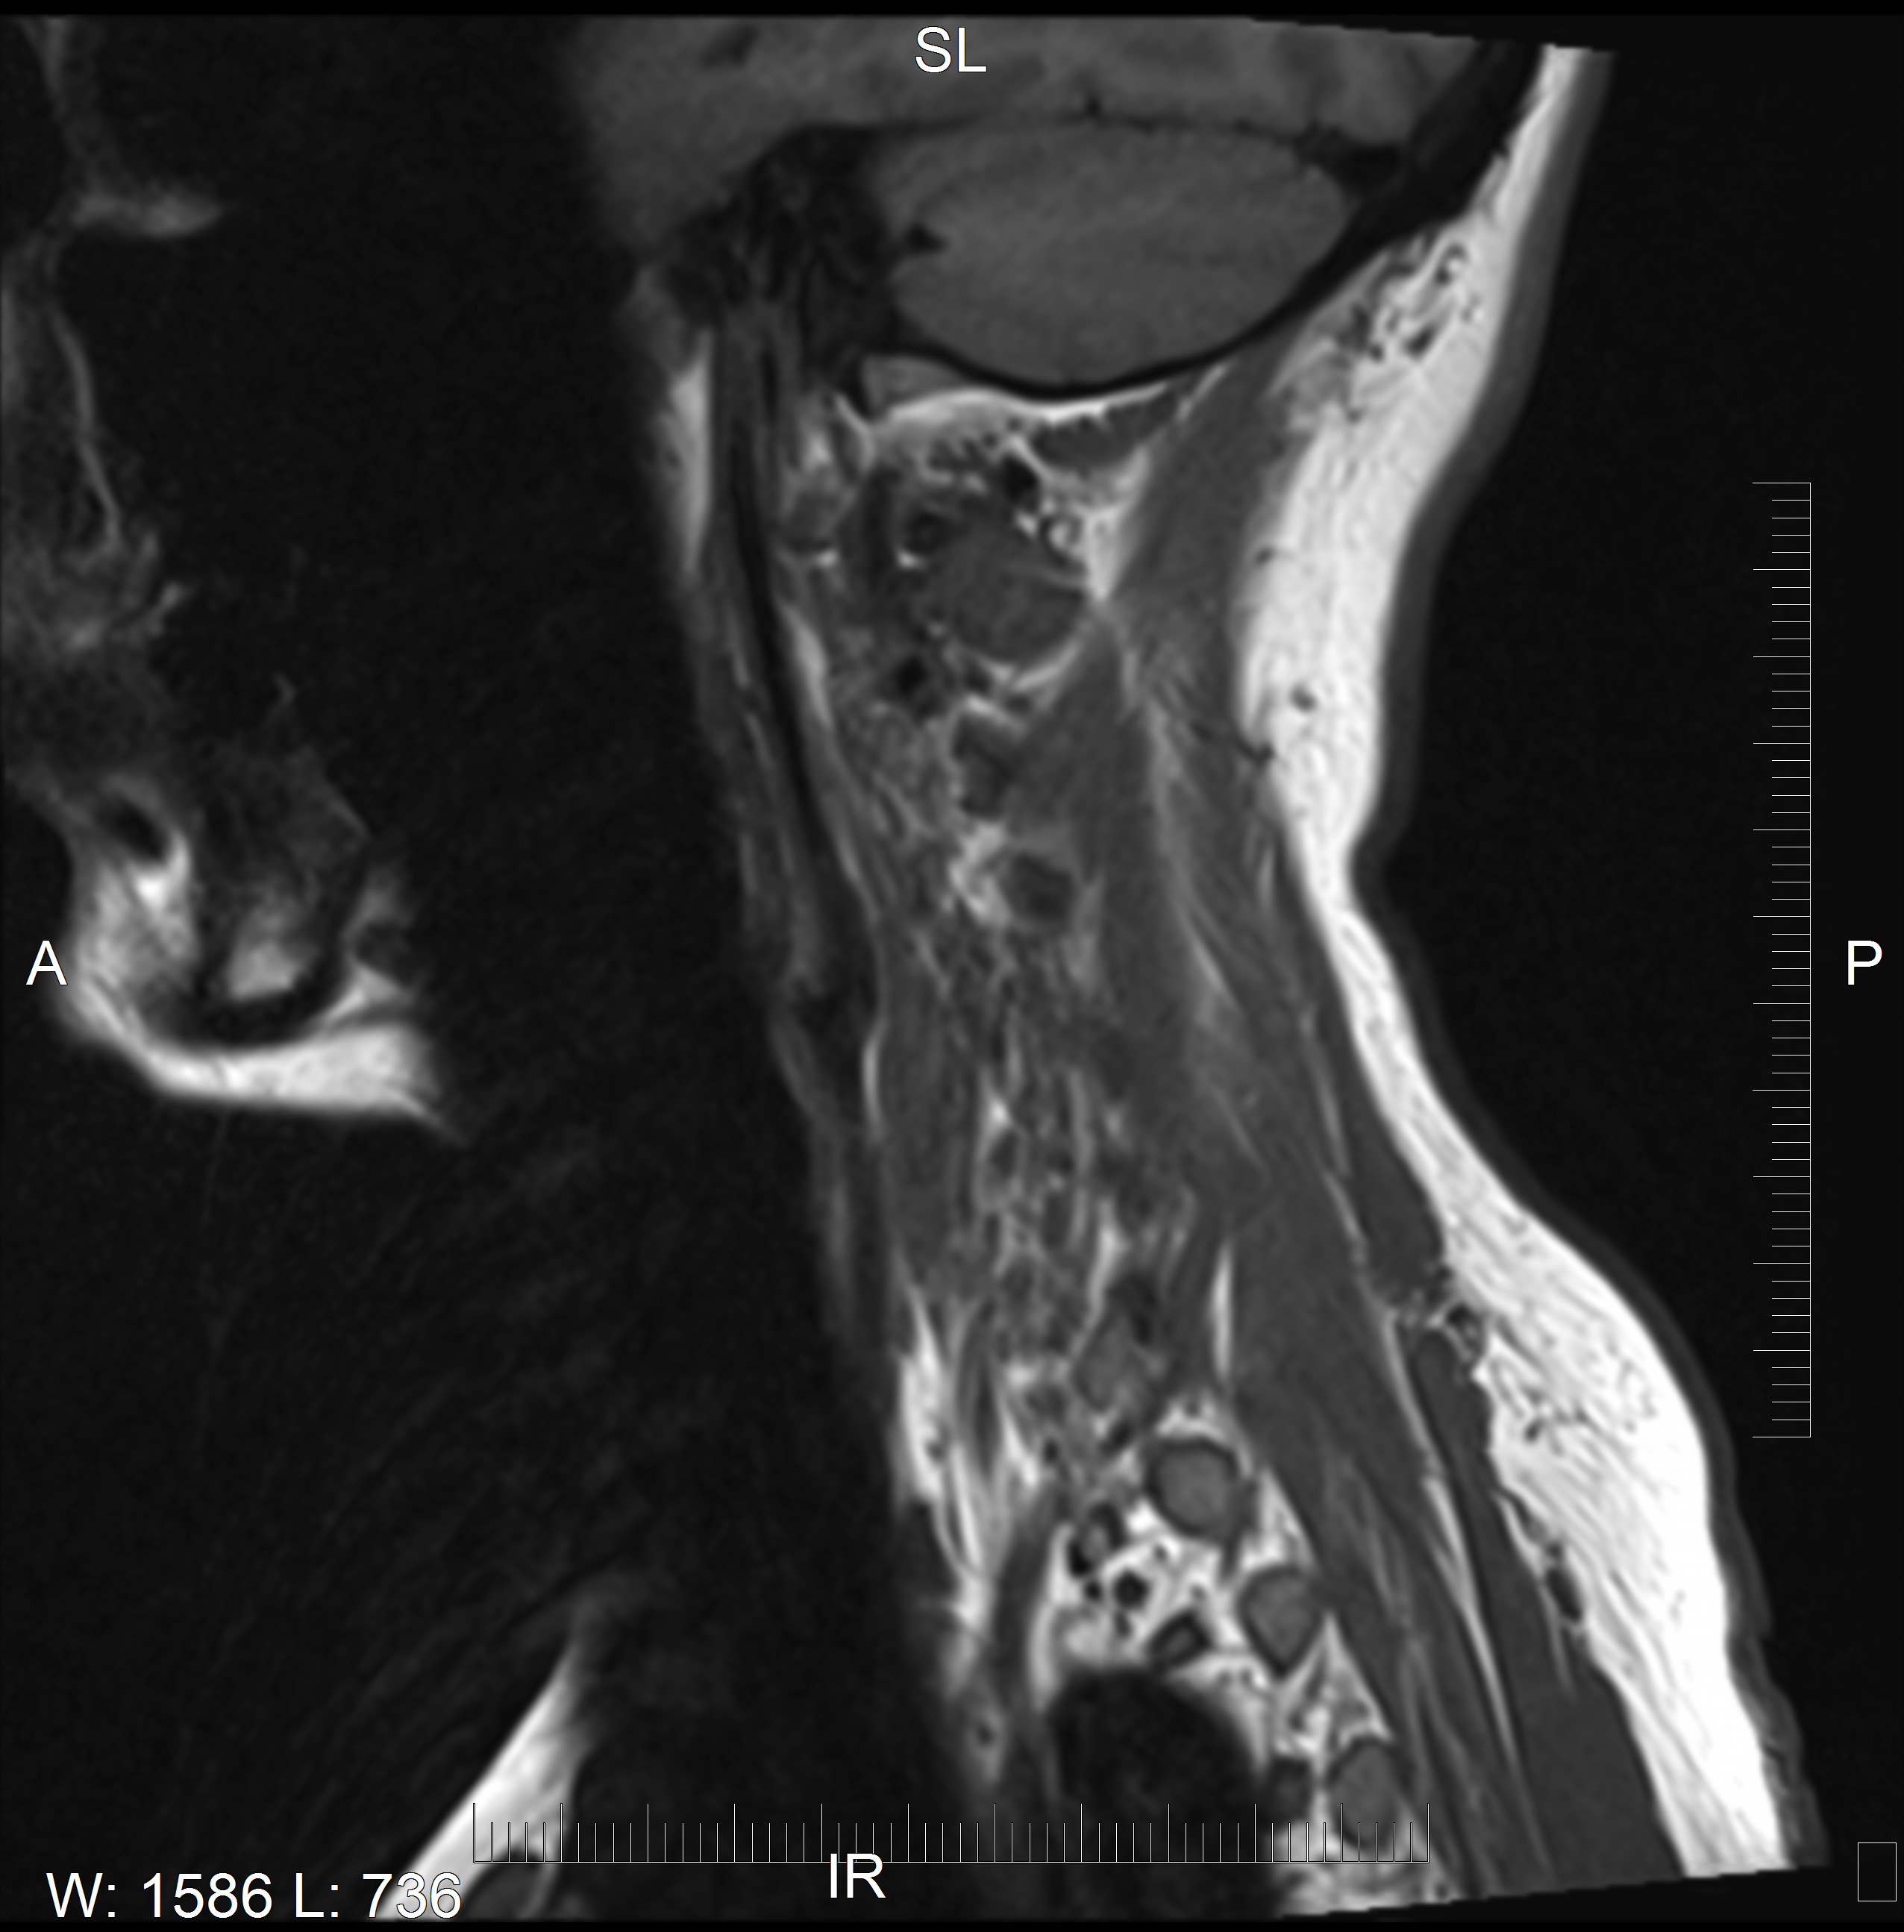

Injured discs in my cervical spine. Dr. Elizabeth Starr Hoefer, D.C dismissed me via text message that told me to go to the ER immediately, and left in fear of the damage she had done. The ER then promptly told me what Dr. Hoefer's text message said, pointing the finger at something else resulting in my pain and injury, was not even possible.

I was fortunate to have MRI images available before and after seeing Dr. Hoefer in Mission Viejo. Unfortunately, the injury I sustained in her care took me a year of pain and suffering to even begin to resolve with an orthopedic surgeon.